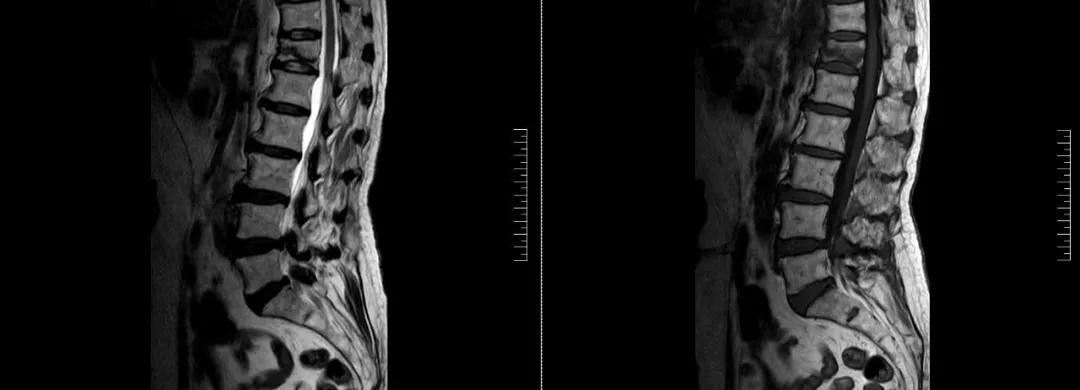

術前磁共振檢查提示腰1椎體新鮮壓縮性骨折